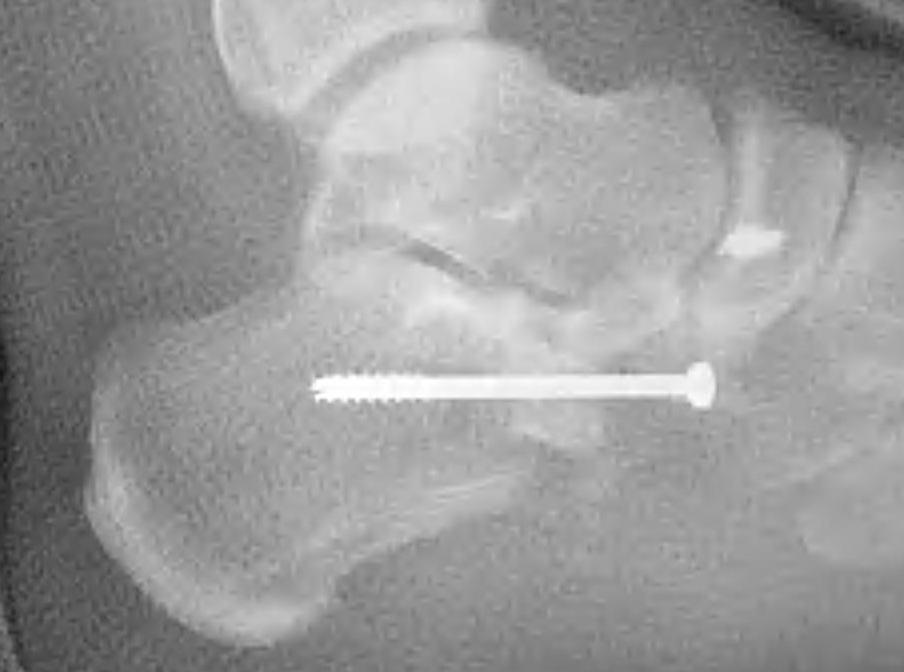

Subtalar arthroeresis

implantimplantimplant

Concept

Types

Endosinotarsal - implant in the sinus tarsi

Exosinotarsal - screw external to the sinus tarsi